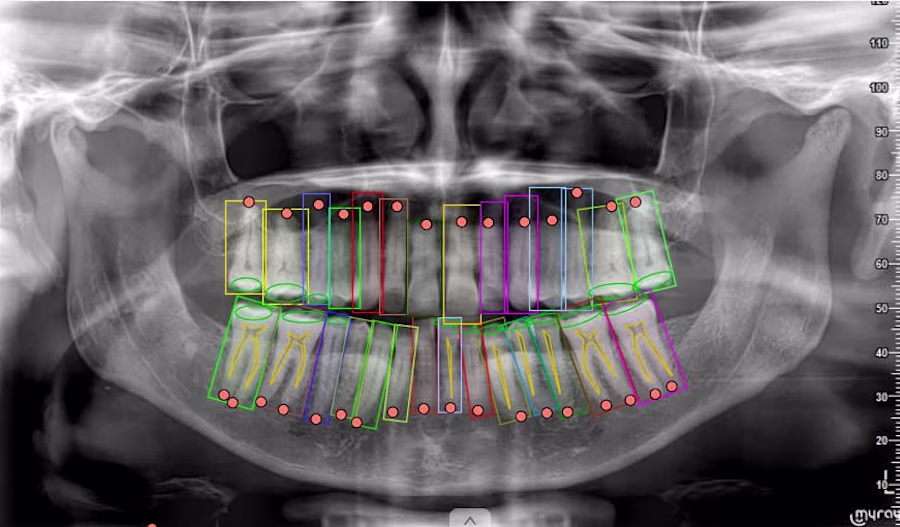

Annotated complex dental X-ray medical imaging datasets used to train AI models for healthcare applications.

The project involved precise labeling of anatomical structures including teeth boundaries, roots, and surrounding regions using polygon and keypoint annotation techniques.

The objective was to generate high-quality training datasets that allow machine learning systems to accurately detect dental structures and support medical imaging analysis.

Responsibilities included: • Image segmentation and polygon annotation • Keypoint labeling for anatomical structures • Dataset preparation for machine learning models • Annotation quality control and validation